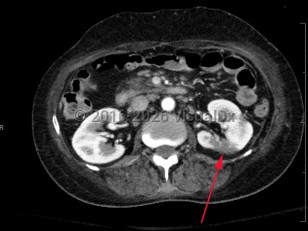

Low back pain, Nausea, 50-59 year old Female

Hydronephrosis

Renal calculus

Ureteral calculus

Perinephric abscessPerinephric abscess